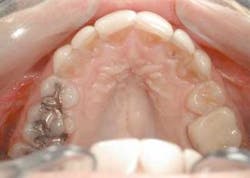

Upon anesthetizing the patient, I decided to remove the old veneers to observe the underlying teeth. I was able to observe the old preparations and the actual color of the teeth. This information will help me with my new preparations (Fig. 6).

null

We found some severely tetracycline-stained teeth that had hardly any preparation. The result was thick teeth (Fig. 7). This is the main reason the ceramist was not able to correct many of the nuances of the smile design we discussed earlier. Adequate preparation is the only way to obtain a fantastic result.